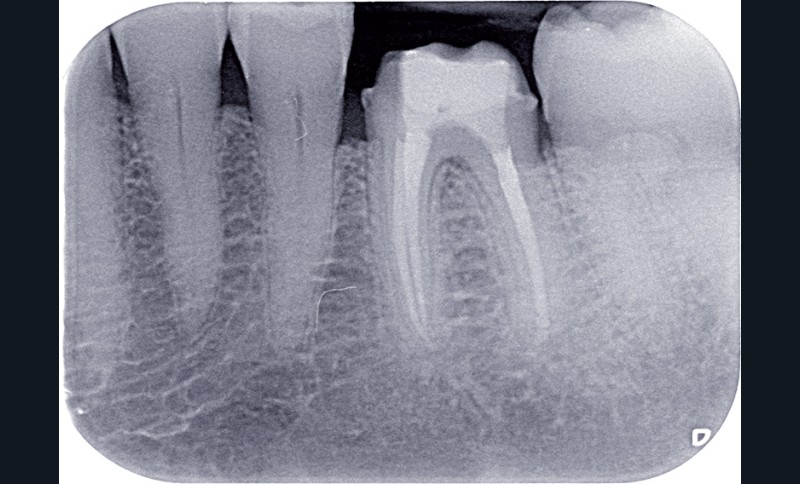

L’OBTURATION CANALAIRE

L’obturation tridimensionnelle canalaire permet de maintenir l’état de désinfection obtenu lors de la préparation chimiomécanique. C’est l’obturation complète de l’ensemble du réseau canalaire, aussi près que possible de la jonction cémentodentinaire. Elle fait partie intégrante de la triade endodontique dont les deux autres composantes sont la mise en forme et l’irrigation. Le praticien est amené à se poser la question suivante : quelle technique d’obturation choisir ? La vraie problématique réside dans la mise en forme. En effet, un canal mal mis en forme sera mal nettoyé et par conséquent mal obturé. Ainsi, les différents…